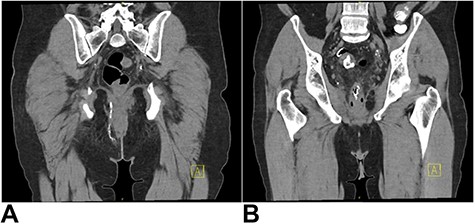

Magnetic resonance imaging (MRI) identified a fistulous tract extending from the sigmoid colon, around the anterior aspect of the anal canal, with small collections in the ischiorectal and ischioanal fat. CT fistulogram showed a long fistulous tract extending from the right peri-anal region to a sigmoid diverticulum above the recto-sigmoid junction (Figs 1 and 2). The patient underwent a second EUA at which a large tract was identified at 9 o’clock, running parallel to the anus and rectum, with no apparent connection to the anus but draining enteric content. The superior extent of the tract was not felt. Colonoscopy showed a benign-appearing, intrinsic moderate sigmoid stenosis measuring 2 cm in length, which was traversed with difficulty.

(A) CT fistulogram showing a long fistulous tract extending from the right peri-anal region, superiorly in the ischiorectal fossa, traversing the inferior aspect of the levator ani and extending around the right of the anal canal and rectum; (B) superiorly, it extended into a thick-walled inflamed segment of sigmoid colon with numerous diverticulae; contrast can be seen entering the sigmoid loop.